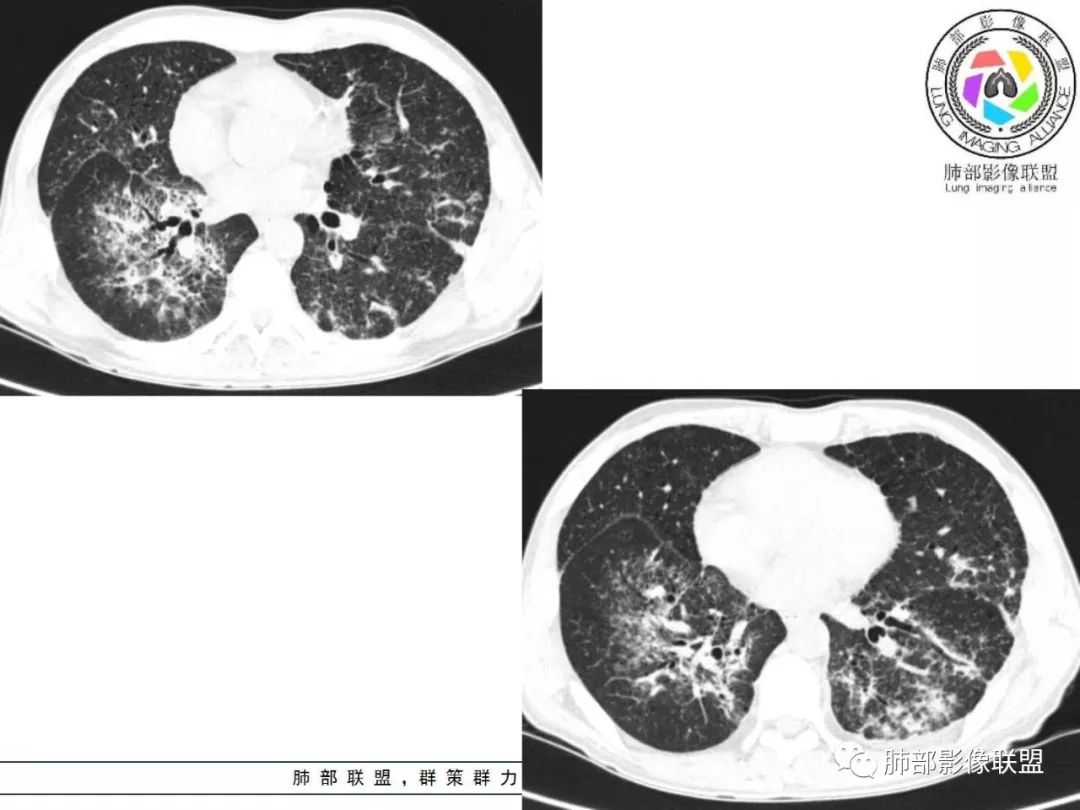

胸部CT:两肺弥漫病灶,磨玻璃影,少许实变,部分累及胸膜,磨玻璃区可见囊?少许胸腔积液,两肺可见结节,支气管血管束增粗,小叶间隔增厚,支气管走形有扭曲扩张,可见纤维化。气肿、大泡。考虑:感染性病变,PCP?查下HIV,CD4,G等。鉴别结核、结缔组织病肺浸润。

55多男性,发热为主诉,体温38℃-39℃多,午后及夜间发热为主,峰值40℃,伴黄痰,CRP高,血糖正常,胸部CT:两肺弥漫病灶,磨玻璃影,少许实变,部分累及胸膜,两肺可见结节,似可见树芽,支气管血管束增粗,小叶间隔增厚,见肺气肿、大泡。考虑感染性病娈,肺结核可能性大。

患者中年男性,发热1月,体温38℃-39℃,峰值40℃,无畏寒、寒战,伴黄痰,CRP升高明显,降钙素原稍升高,血沉、血糖正常。胸部CT:两肺弥漫病变,磨玻璃影+点片渗出,部分累及胸膜,磨玻璃区边界清楚,少许胸腔积液,两肺支气管血管束增粗,小叶间隔增厚,部分支气管走形有扭曲扩张,可见肺气肿、右肺尖肺大泡及部分纤维化改变。综合考虑:感染性病变。结核或PCP可能性大,鉴别风湿免疫、结缔组织疾病肺浸润和腺癌等恶性病变。

两肺弥漫性病变,沿支气管血管束分布,部分细支气管轻度扩张,两上中肺为主,部分累及胸膜下,部分磨玻璃影,部分纤维化,肺气肿肺大疱背景,胸膜增厚,少量积液,病程一月余,crp高反复发热,两肺门区增大钙化淋巴结,间质性疾病,考虑淋巴增殖性病变为主,结核可能性大,待鉴别NTM,结节病,LIP,PCP纤维化

病变一般沿血管支气管束分布或小叶分布,一般上肺多于下肺(这与常见继发性肺结核分布相若)。

常会伴有其他继发性肺结核病灶,如斑片影、结节影,树芽征,新旧不等改变。

2. 肺气肿背景(小叶中心性肺气肿);双肺多发病灶整体沿血管支气管束及胸膜下分布,以上叶及下叶背段分布为主,有实变及GGO,边界清楚,有树芽,小叶间隔及中央间质增厚,叶间裂见到多发结节,部分支气管不规则牵拉扩张,提示病灶纤维化明显,结合临床病史,考虑病灶为间质性感染,肺门及纵隔内有钙化淋巴结,小叶间隔结节,考虑淋巴道增值性疾病可能,综合常规要怀疑间质性肺结核。